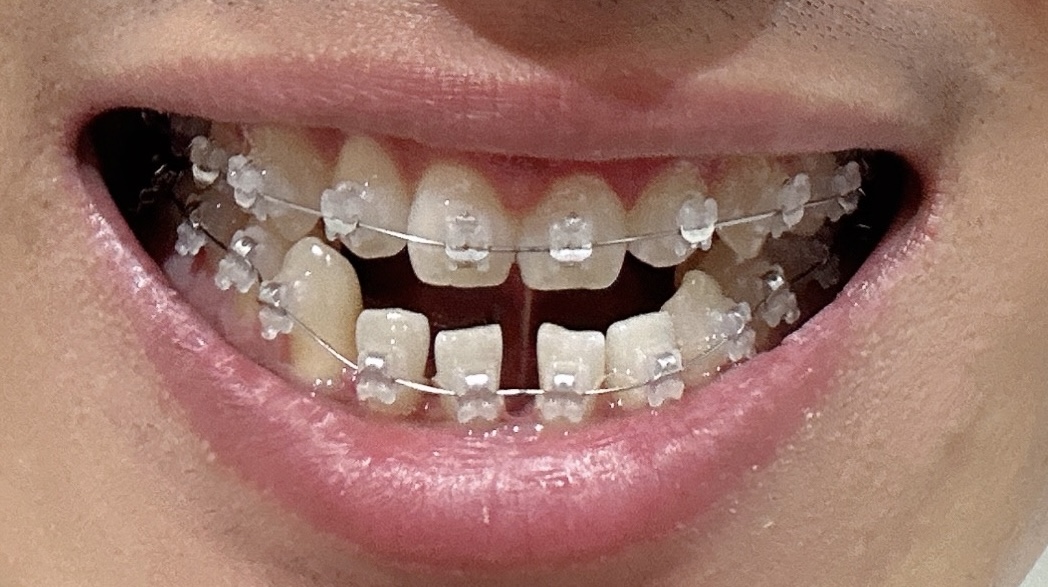

10월1일 교정 한달 차

교정 한달이 지난 모습을 보니까 확실히 앞니의 모습이 많이 괜찮아졌습니다. 처음에는 정말 아팠는데 말이죠. 벌어진 부분이 많이 사라졌고, 돌아갔던 부분도 어느정도 일자로 반듯해지고 있는게 보이네요. 정말 신기하죠? 우선 앞니부터 돌리고 안쪽으로 밀어넣을 예정이라고 하니까요. 1년 6개월 정도 예상을 하고 있는데 벌써 이렇게 반듯해진 모습이 기대가 됩니다.

힘든 부분은 가장 처음에 교정하고 이가 정말 아팠는데요. 이번에는 치과에 다녀와서 밥을 먹어도 엄청 이가 아프지는 않았어요. 다음에 조으고 안쪽으로 밀어 넣기 시작하면 조금 더 아플거 같다고 하는데요..